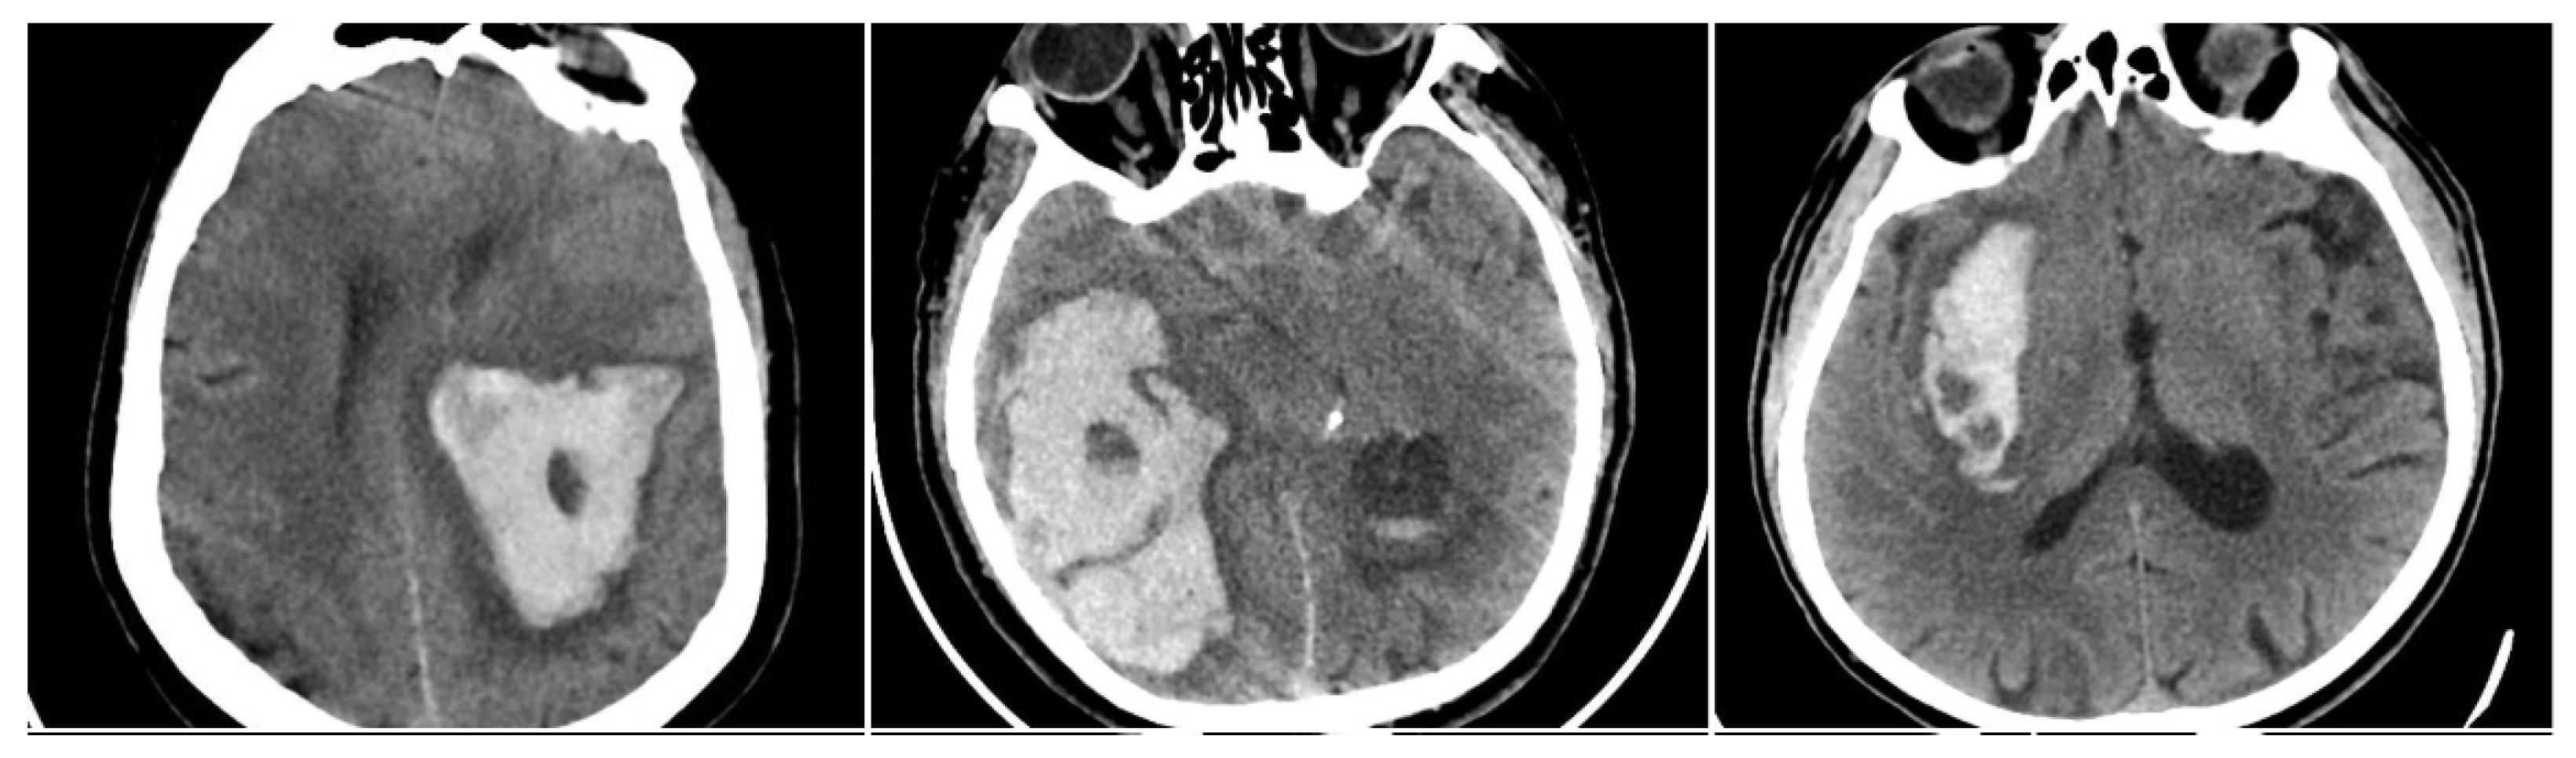

The Satellite Sign (SS) was identified when a small (≤10 mm) hyperdense hemorrhagic focus lay within 20 mm of, but separate from, the main clot on at least one CT slice (SS = 1 if present, otherwise 0) (Figure 4) [12].

Figure 4. Satellite Sign (SS)—three examples from our cohort.

Figure 7. Intracerebral hemorrhage from the subgroup with in-hospital mortality, demonstrating a high incidence of NCCT signs. (AC) BHS + IRS + SS. (D) BHS + BS + IRS. (EG) BS + IRS + SS.